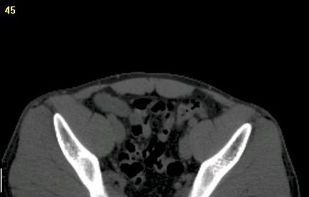

MedSeg is described as 'Online tool for AI-enhanced medical image segmentation of radiological images (CT and MRI). Works with DICOM and NIfTI using Chrome' and is an website. There are four alternatives to MedSeg, not only websites but also apps for Windows, Linux and Mac. The best MedSeg alternative is 3D Slicer, which is both free and Open Source. Other great sites and apps similar to MedSeg are AMIDE, InVesalius 3 and 3D-DOCTOR.